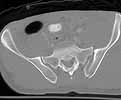

Here are some interesting plain films and CT images for a 22 yo male involved in an auto accident who was then struck as a pedestrian when he exited the vehicle.

Preop CT

He has a left sided sacroiliac injury with an associated posterior iliac fracture, femoral head fracture, femoral neck fracture with extruded head-neck fragment, and posterior wall acetabular fracture with osteochondral impaction.